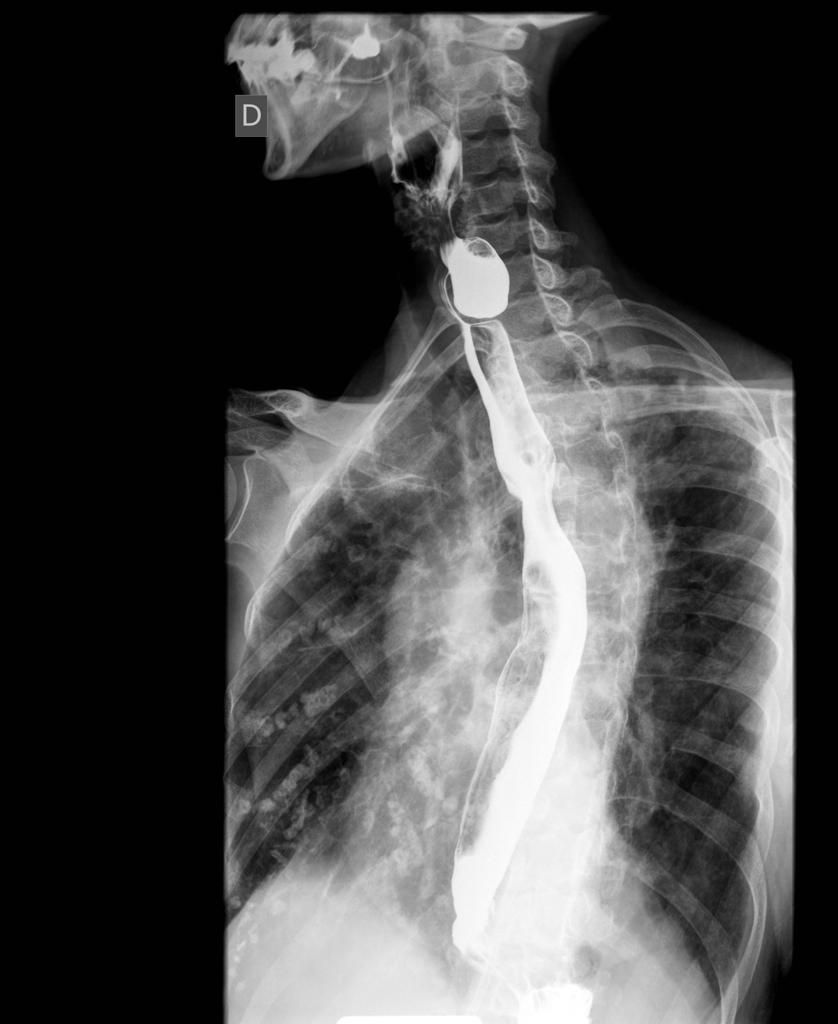

A zenker diverticulum is a pseudo-diverticulum characterized by outpouching of hypopharynx through Killian’s triangle secondary to weakness of muscles. The patient presents with complaints of dysphagia, regurgitation, and halitosis. The barium swallow examination is indicated to diagnose zenker diverticulum. The radiological finding suggesting presence of Zenker diverticulum are: - A diverticulum arising near the pharyngo-esophageal junction. - Outpouching on swallowing at level of C5 and C6. Reference: https://radiopaedia.org/articles/zenker-diverticulum-1 Image via: https://radiopaedia.org/cases/zenker-diverticulum-1